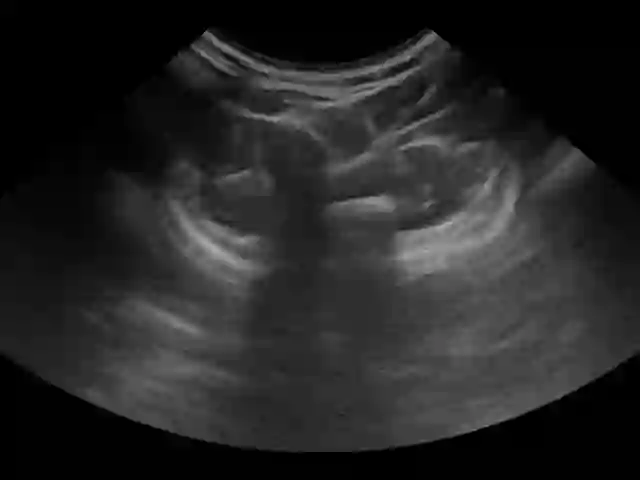

Three-dimensional (3D) freehand ultrasound (US) reconstruction without a tracker can be advantageous over its two-dimensional or tracked counterparts in many clinical applications. In this paper, we propose to estimate 3D spatial transformation between US frames from both past and future 2D images, using feed-forward and recurrent neural networks (RNNs). With the temporally available frames, a further multi-task learning algorithm is proposed to utilise a large number of auxiliary transformation-predicting tasks between them. Using more than 40,000 US frames acquired from 228 scans on 38 forearms of 19 volunteers in a volunteer study, the hold-out test performance is quantified by frame prediction accuracy, volume reconstruction overlap, accumulated tracking error and final drift, based on ground-truth from an optical tracker. The results show the importance of modelling the temporal-spatially correlated input frames as well as output transformations, with further improvement owing to additional past and/or future frames. The best performing model was associated with predicting transformation between moderately-spaced frames, with an interval of less than ten frames at 20 frames per second (fps). Little benefit was observed by adding frames more than one second away from the predicted transformation, with or without LSTM-based RNNs. Interestingly, with the proposed approach, explicit within-sequence loss that encourages consistency in composing transformations or minimises accumulated error may no longer be required. The implementation code and volunteer data will be made publicly available ensuring reproducibility and further research.